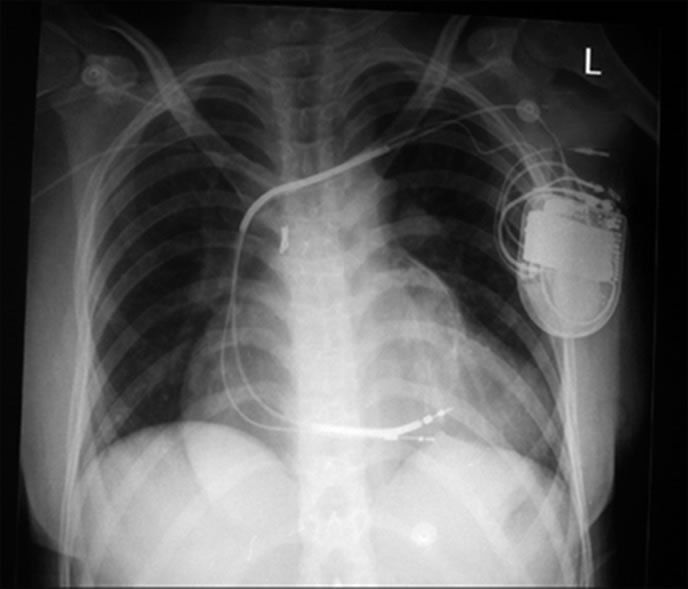

An implantable cardioverter defibrillator (ICD) can be a life-saving device for people whose hearts sometimes beat in an unhealthy rhythm. But because ICDs must be surgically implanted in the chest or abdomen, and because they emit electrical shocks to the heart to restore a healthy rhythm, there are often concerns among patients and physicians that ICDs arent appropriate for older patients.